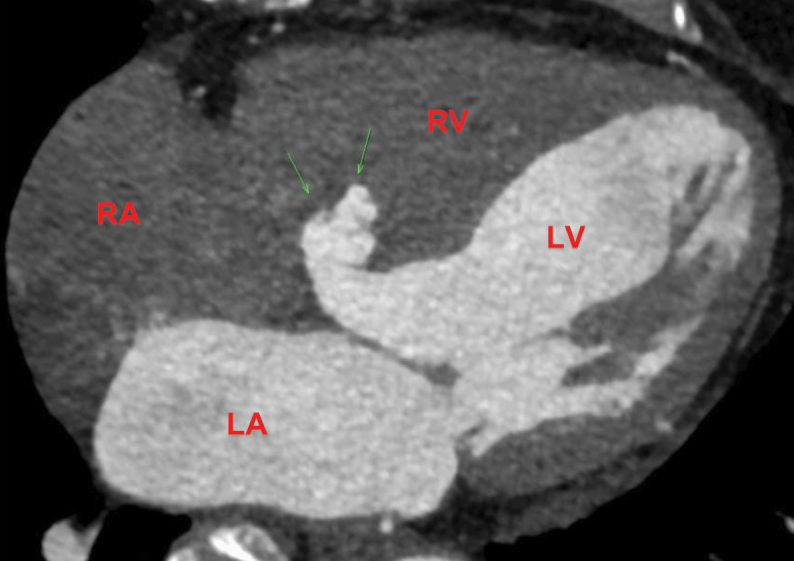

值得注意的是,发现了一个16mm宽颈的风袋状室间隔膨出瘤,同时存在卵圆孔未闭和左向右分流(图1,图2)。

图2. 心脏CTA显示室间隔膨出瘤(箭头所示)。

RV(右心室);RA(右心房);LV(左心室);LA(左心房)